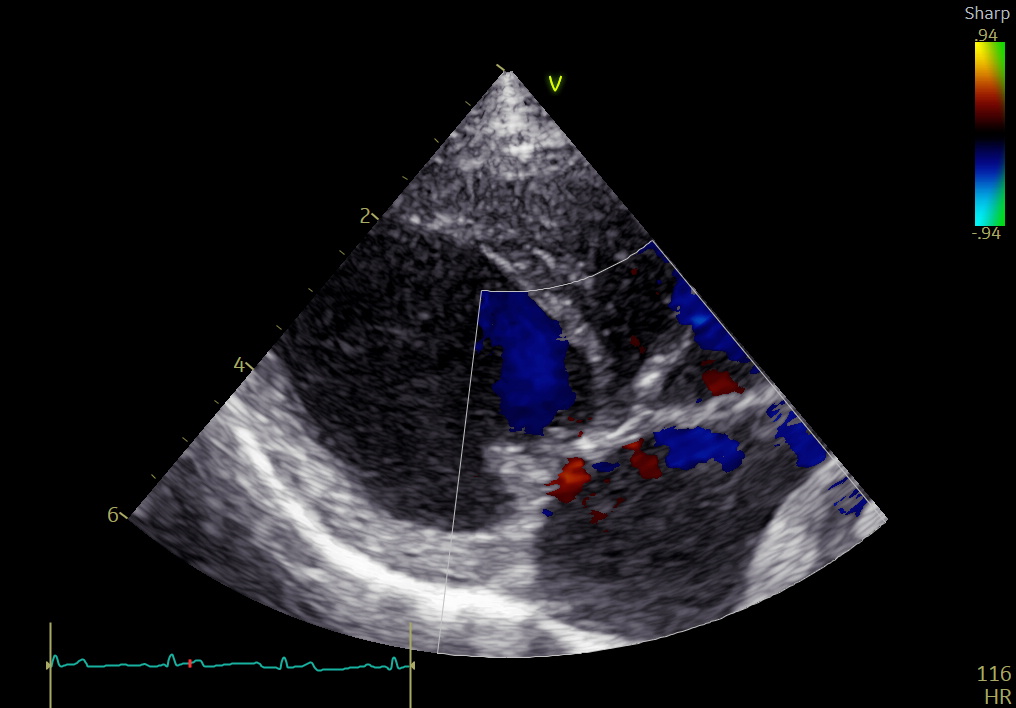

手術前

手術後

心臓超音波検査では、

• LA/Ao:2.70

• LVIDDN:2.37

• 重度僧帽弁逆流

を認め、左房・左室ともに著明な拡大が確認されました。

• 僧帽弁逆流は消失

• LA/Ao:1.43

• LVIDDN:1.62